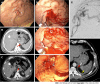

Non-variceal upper gastrointestinal bleeding (NVUGIB) is a common gastroenterological emergency associated with significant morbidity and mortality. Gastroenterologists and other involved clinicians are generally assisted by international guidelines in its management. However, NVUGIB due to peptic ulcer disease only is mainly addressed by current guidelines, with upper gastrointestinal endoscopy being recommended as the gold standard modality for both diagnosis and treatment. Conversely, the management of rare and extraordinary rare causes of NVUGIB is not covered by current guidelines. Given they are frequently life-threatening conditions, all the involved clinicians, that is emergency physicians, diagnostic and interventional radiologists, surgeons, in addition obviously to gastroenterologists, should be aware of and familiar with their management. Indeed, they typically require a prompt diagnosis and treatment, engaging a dedicated, patient-tailored, multidisciplinary team approach. The aim of our review was to extensively summarize the current evidence with regard to the management of rare and extraordinary rare causes of NVUGIB.